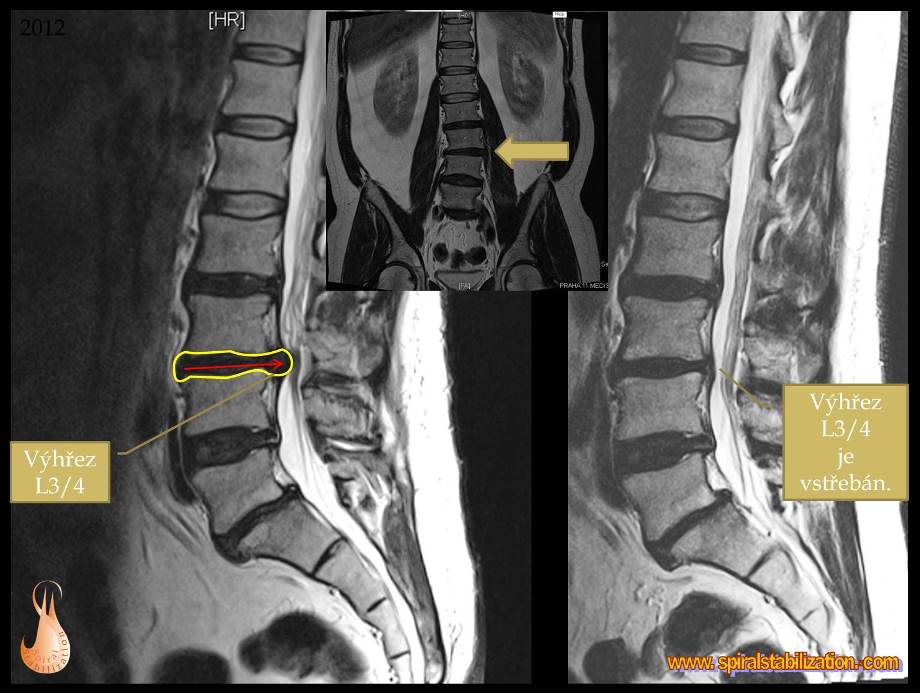

Výsledky hernia L3/L4